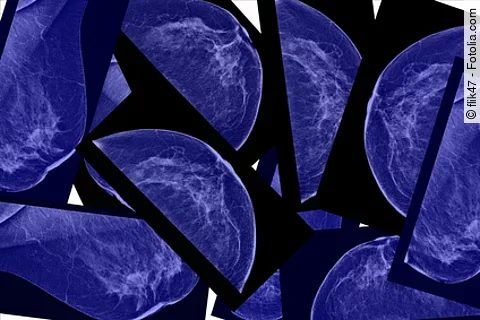

BI-RADS bei Brustkrebs: Geschulter Radiologenblick sagt Histologie voraus

flik47 - Fotolia.com

Die Brustkrebssterblichkeit lässt sich dank besserer Diagnosemöglichkeiten drastisch senken – und das ist nicht nur den bildgebenden Geräten zu verdanken. Vielmehr spielt der menschliche Faktor eine große Rolle: Ein Radiologe, der die Läsionen begutachtet und bewertet, trägt erheblich zur Prognose bei.